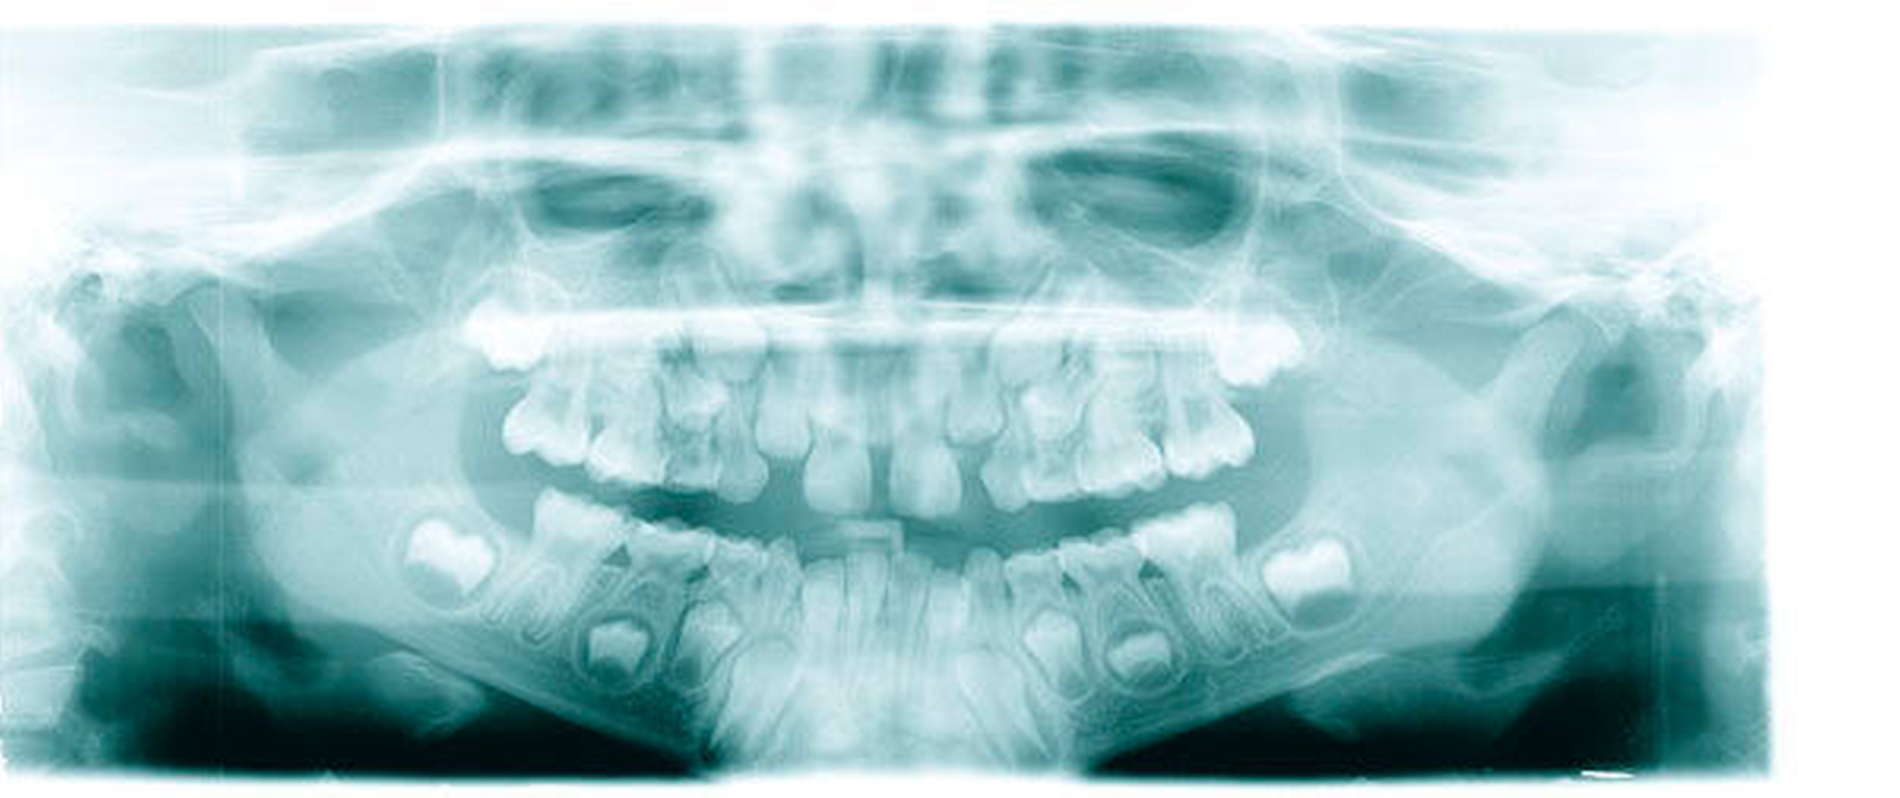

Befund:Abgesehen von einer insgesamt verzögerten körperlichen und dentalen Entwicklung aufgrund der Vorerkrankung, zeigte sich der extraorale Befund unauffällig, der intraorale Befund zeigte ein Wechselgebiss. An allen ersten Milchmolaren konnte Approximalkaries festgestellt werden. Alle Sechsjahrmolaren sowie die Schneidezähne im Ober- und im Unterkiefer waren, unterschiedlich ausgeprägt, von MIH betroffen. Das Zähneputzen und Essen wurde zunehmend zur Belastung aufgrund der Schmerzempfindlichkeit. Außerdem wurde Substanzverlust an Zahn 46 bemerkt (Abbildungen 9 und 10).

Therapie:Nach Befundaufnahme und Besprechung mit den Eltern und dem hinzugezogenen Kieferorthopäden wurden alle Behandlungsalternativen ausführlich besprochen. Aufgrund der Vorerkrankung und der täglichen Belastung des Kindes entschieden sich die Eltern für eine möglichst schnelle und langfristige Lösung. Außerdem sollte die Ästhetik, also die Zahnfarbe, auch im Seitenzahnbereich, mit berücksichtigt werden.

Gemeinsam wurde entschieden, dass die nicht so schmerzempfindlichen Frontzähne zunächst so belassen und gegebenenfalls später, wenn die optimale Zahnstellung erreicht ist, mit Füllungen oder Veneers versorgt werden. Die Zähne 16, 26 und 46 sollten mit Keramikkronen versorgt werden (Abbildungen 11 bis 13). Der weniger stark betroffene Zahn 36 sollte, wenn möglich, mit einer Kunststofffüllung versorgt werden. Eine mögliche spätere Extraktionstherapie je nach Engstand oder auch anstelle einer gegebenenfalls notwendigen Weisheitszahnentfernung wurde abgeklärt. Hinzu kam eine Füllungstherapie für die Zähne 64, 74 und 84. Der Zahn 54 wurde extrahiert, da die Wurzelresorption für eine Pulpotomie schon zu fortgeschritten war.

Aufgrund der Vorbelastung der jungen Patientin und der starken Schmerzempfindlichkeit wurde die Behandlung in ITN durchgeführt. Das Zementieren der Keramikkronen (mit Oxidkeramik/e.max) konnte wiederum in der Praxis durchgeführt werden (Abbildungen 14 bis 16), da die Patientin großes Vertrauen zeigte und sich ihren Wunsch von schmerzfreien Zähnen erfüllen wollte. Ansonsten wäre optional noch zusätzlich zur Lokalanästhesie die Lachgasbehandlung anstelle eines zweiten kurzen ITN-Termins möglich gewesen.